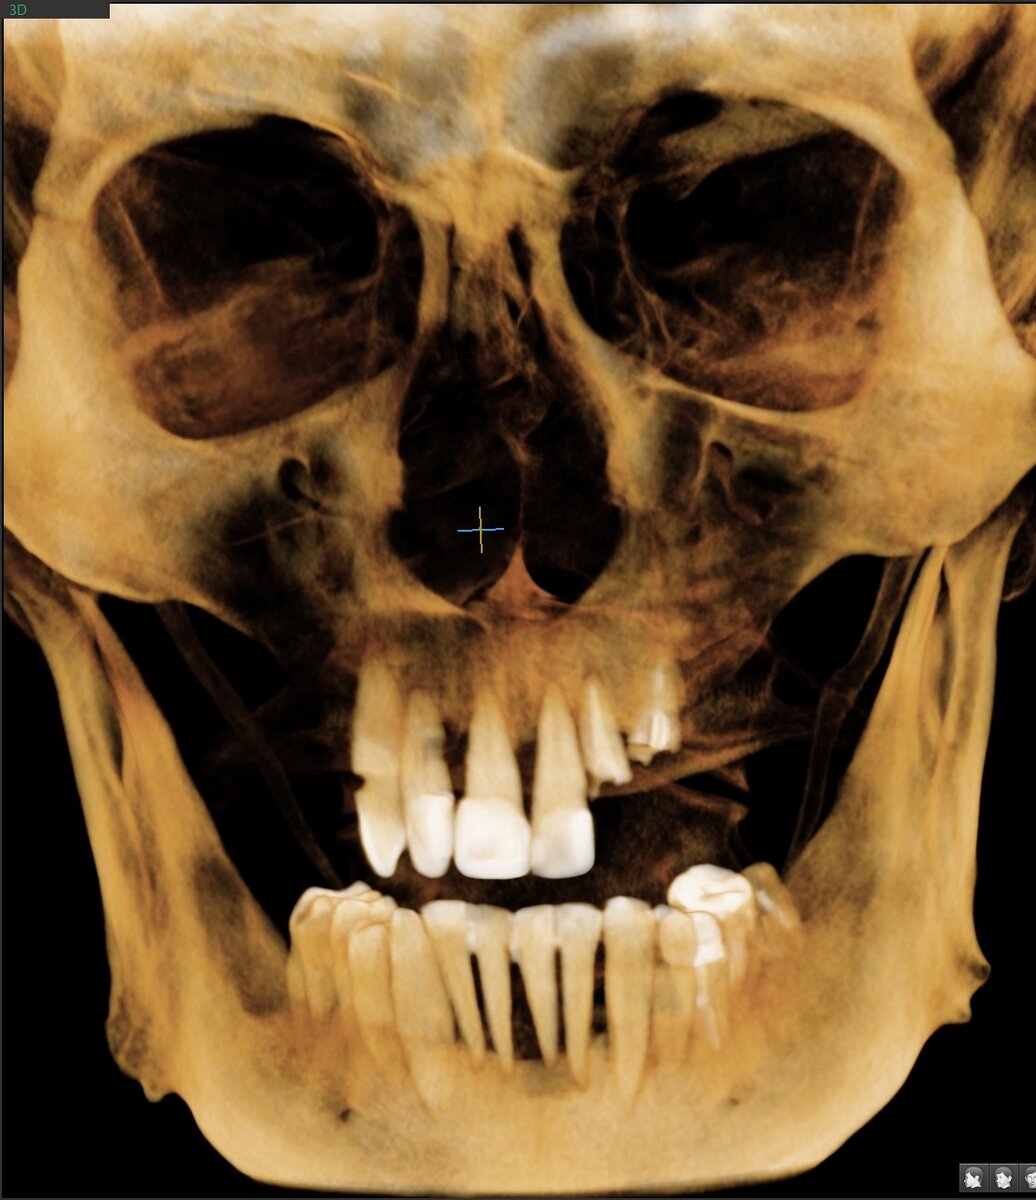

Имплантаты "всё на 4-х" установлены в кость верхней челюсти:

1. Позиция зуба 1.4 - отлично.

2. Позиция зуба 1.2 - блеск, не придраться.

3. Позиция зуба 2.2 - и снова красота.

4. Позиция зуба 2.4 - миллиметраж, который позволяет безопасно осуществить шаблон, пазуха цела и невредима.